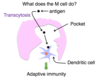

Langerhans cells = Immune cells in epidermis

- Dendritic cells (stratum spinosum)

Langerhans Cells

- Immune cells

Type of dendritic cells